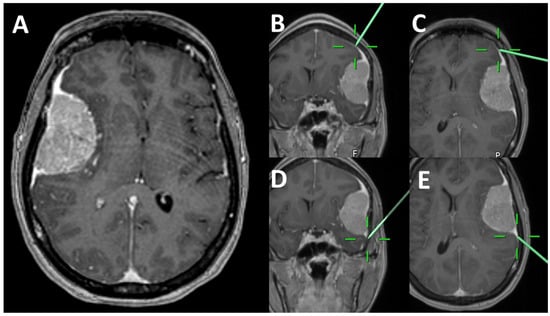

2.2. Radiological Analysis